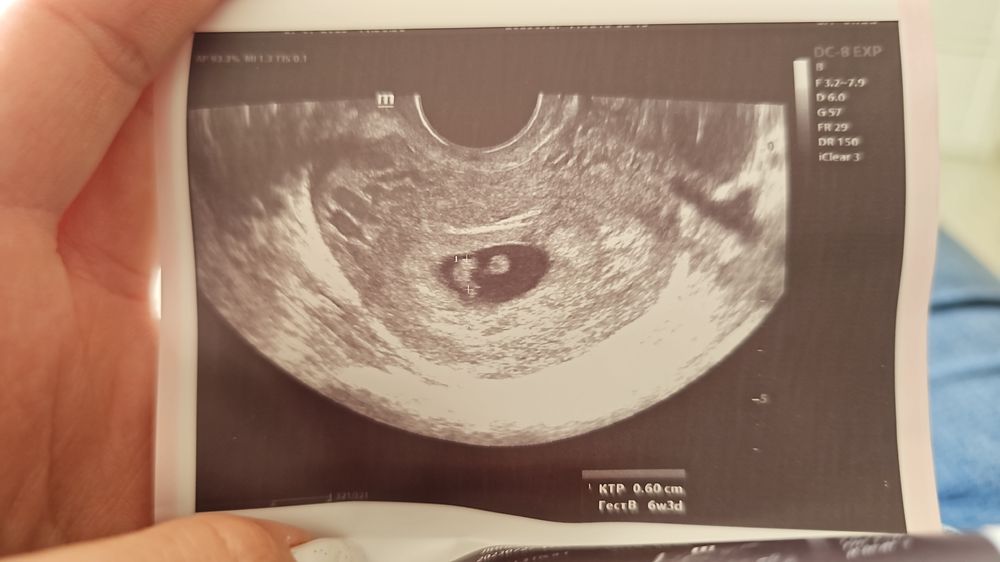

По узи у мелочи все хорошо, КТР соответствовал сроку, сердцебиение 130, локация по передней стенке, от рубца далеко, рубец 6,8 мм... по задней миома моя на месте. Оперироваться буду у Кунешко Нарта (наш заведующий роддомом), он вырежет мне сразу и миому на операции КС.